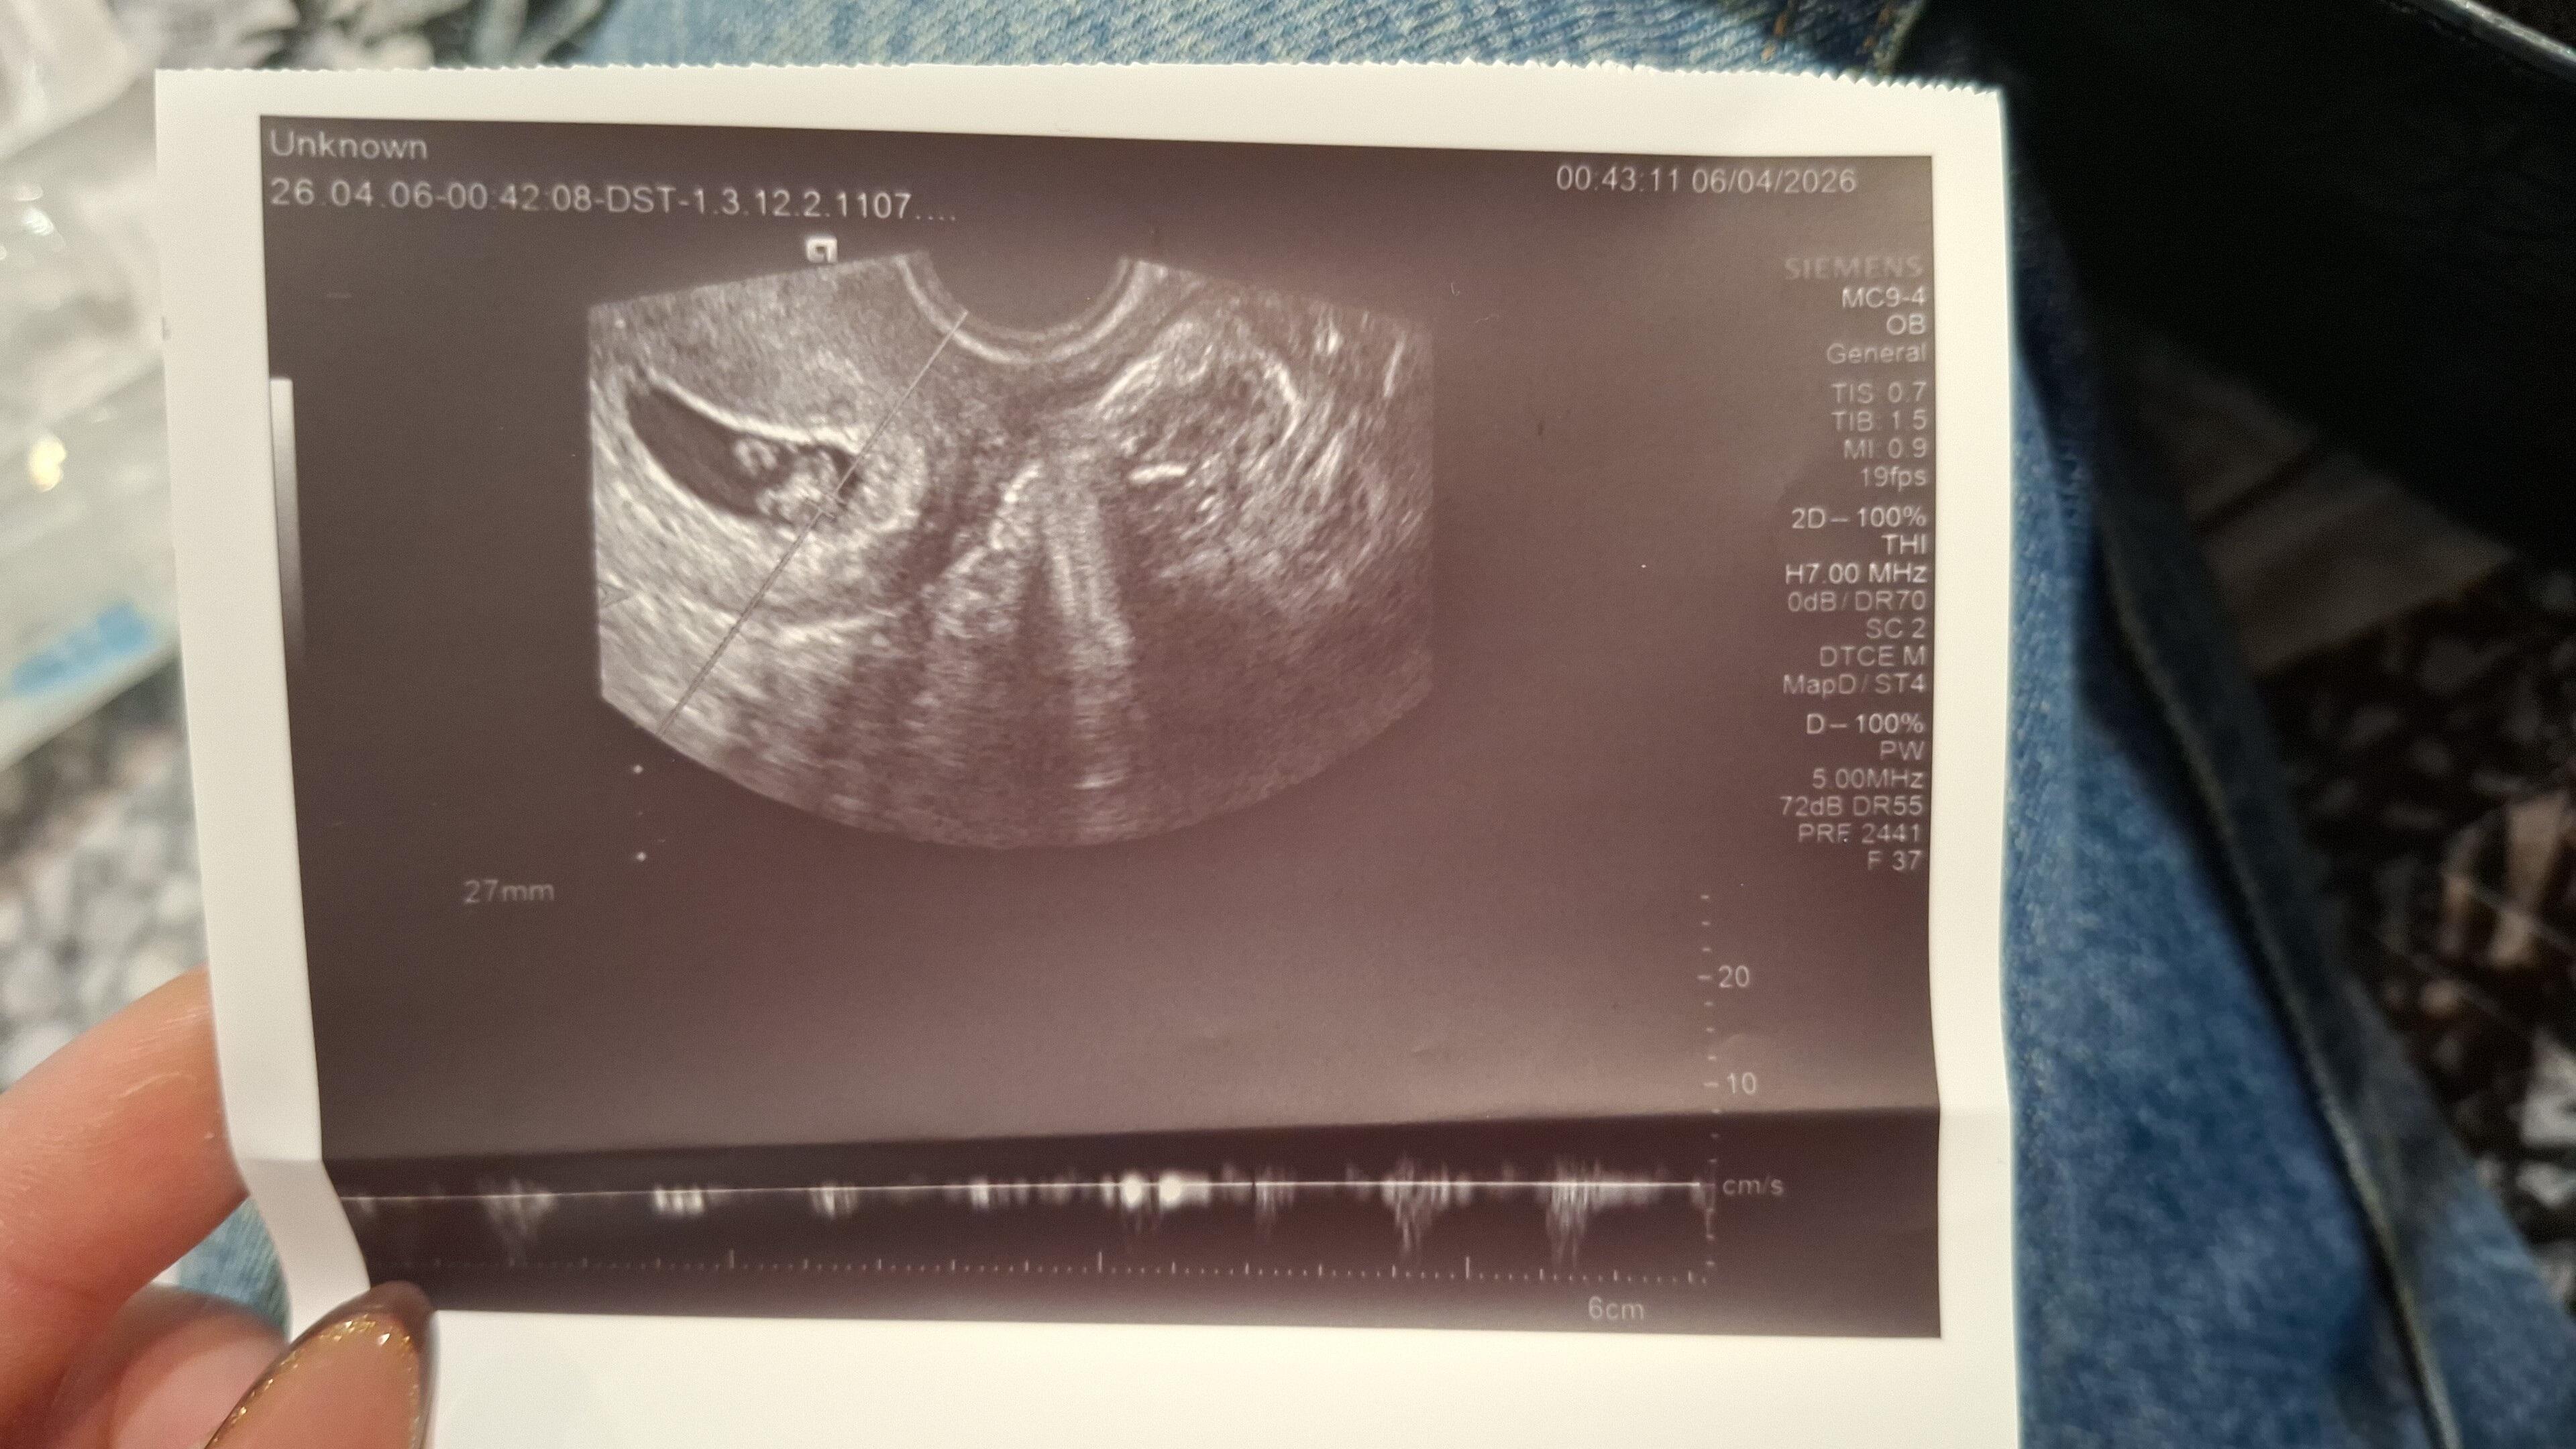

Regle göre 7 haftalık gebeyim. Dün doktora gitmişdim kahverengi leke görmüştüm diye. Doktor 6 haftalık dedi, kalp atışını dinletti. Herşey normal dedi. Ama kalp atışı zayıftı bana göre. Doktor daha kalbi yeni oluşmuş o yüzden normal dedi. Başına gelen oldumu? Bazıları kalp atışı zayıfsa durabilir demişti. Ola bilirmi öyle bişey?

6. haftada zayıf değil, normali budur. 6. haftada kalp atışı yeni başladığı için dakikada 90-110 atım civarında olabilir ve bu sana zayıf gelebilir. sağlıklı gebelik kalp atışı zamanla hızlanır. 1-2 hafta sonra kalp atışı belirgin şekilde güçlenmiş ve hızlanmış olacaktır. Kahverengi lekelenmede sürekli olmadığı, kırmızıya dönmediği ve şiddetli ağrı eşlik etmediği sürece tedirgin olma. Sağlıklı bir gebelik geçirmen dileğiyle ![]()

Ben resminn üzerinde kalp atışını dakikada kaç atım olduğunu göremedim. Resimdeki 90-110 arası gibimi?